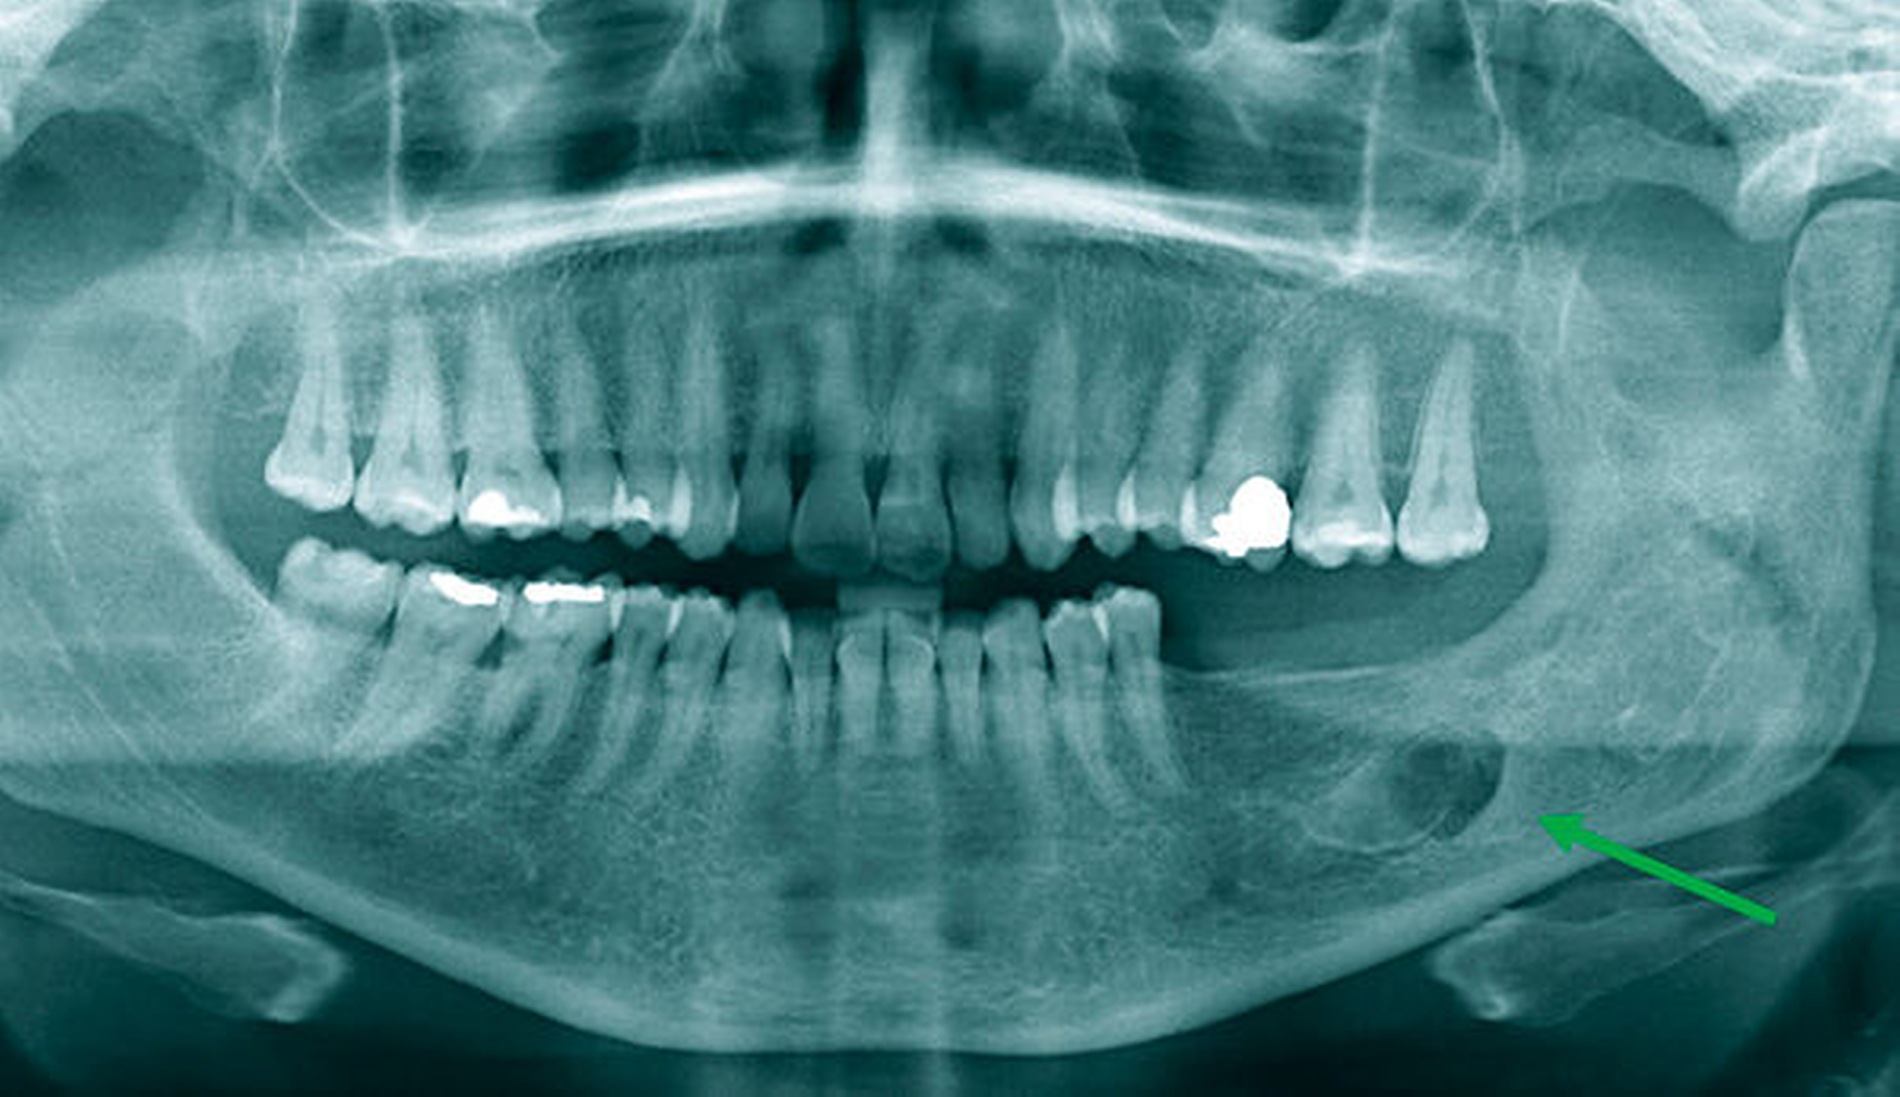

Eine 52-jährige Patientin stellte sich 2015 zur regulären Kontrolle nach der Entfernung einer Keratozyste im linken Unterkiefer im Bereich des distalen Corpus und aufsteigenden Unterkieferastes vor (Abbildung 1). Es hatte sich damals um eine unilokuläre Läsion gehandelt. Der Befund war über eine laterale Osteotomie im Sinne einer Zystektomie entfernt worden.

Bis 2017 hatten sich keine Auffälligkeiten gezeigt. Nun stellte sich in der Kontrolle mittels Panoramaschichtaufnahme radiologisch der Verdacht auf ein Rezidiv. Im Bereich des Corpus-Kieferwinkel-Übergangs zeigte sich eine blasig anmutende Transluzenz knapp oberhalb der Projektion des N. alveolaris inferior. Sensibilitätsausfälle lagen nicht vor. Die erweiterte Bildgebung mittels digitaler Volumentomografie bestätigte eine Lage direkt cranial des Nervens mit einem Durchmesser von 0,7 cm x 0,5 cm x 0,5 cm (Abbildung 2).